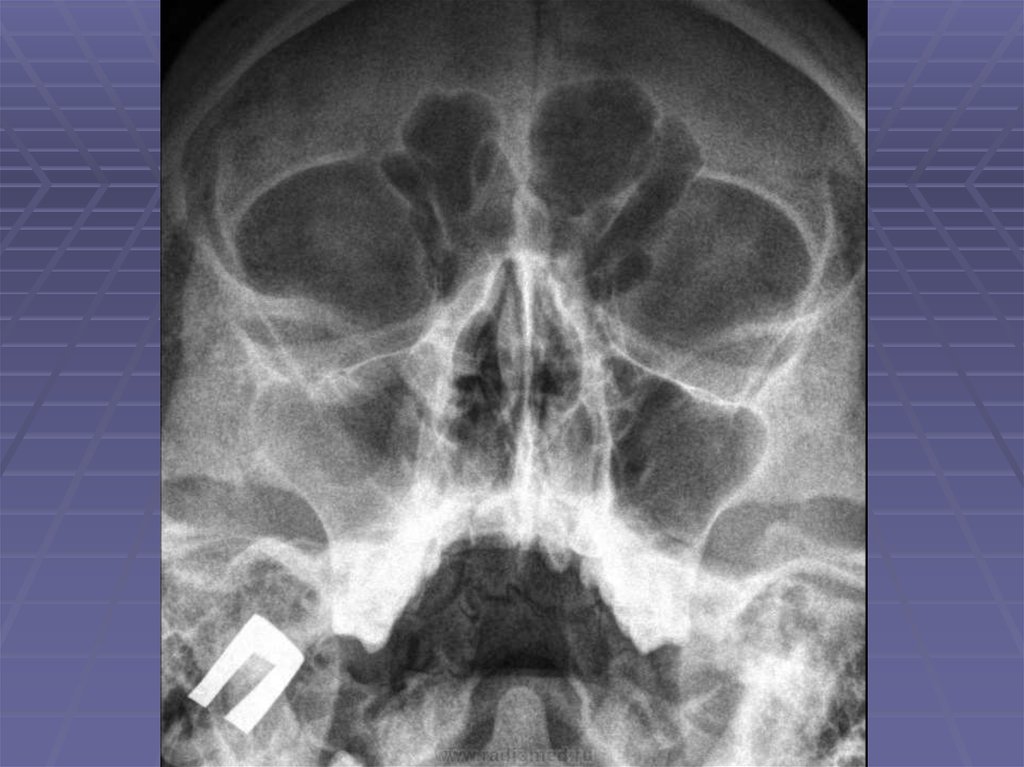

Череп